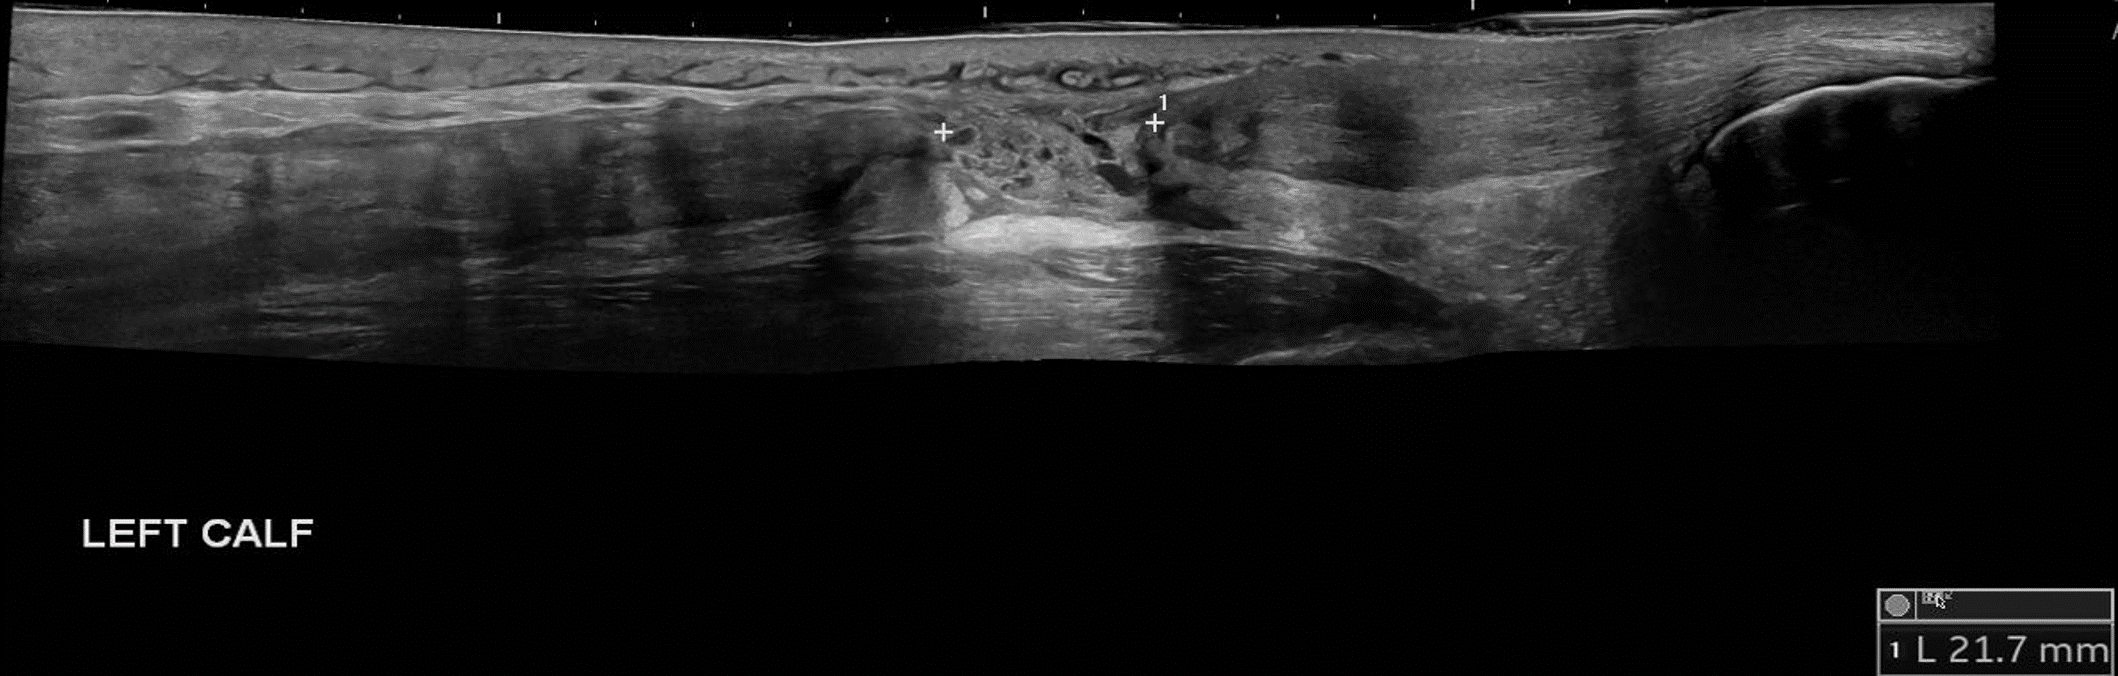

Although classically seen in people who play tennis, it can also be induced by playing squash, skiing, and athletics. Therefore, it typically occurs in active individuals. Extension of the knee and forced dorsiflexion of the ankle seem to be the most frequent biomechanical causes of the injury, which result in rupture of the medial head of the gastrocnemius muscle or injury to the gastrocnemius-soleus aponeurosis, without evidence of muscle rupture.

Ultrasound findings show a hypoechoic linear abnormality (yellow arrows).